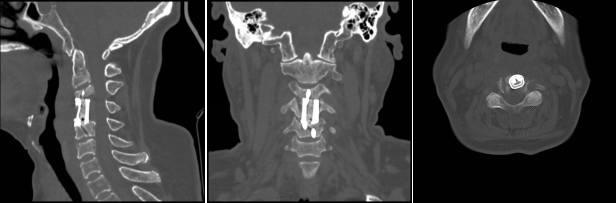

術(shù)后影像學顯示,植入內(nèi)植物位置滿意,與終板匹配性良好,穩(wěn)定性佳。術(shù)后患者生命體征平穩(wěn),癥狀明顯緩解,活動良好,目前已出院。

經(jīng)過周密細致的術(shù)前討論,脊柱外科團隊最終決定為該患者擬行頸椎病灶清除、椎管減壓+植骨融合術(shù),考慮患者高齡,又有骨質(zhì)疏松,為更好保障重建穩(wěn)定性,采用3D打印進行術(shù)前規(guī)劃設計假體進行植入,此款融合器是國內(nèi)首款SLM激光打印融合器,具有解剖匹配、骨融合確切等優(yōu)勢,為取得優(yōu)良手術(shù)效果打下了堅實基礎。

患者入院后完善相關(guān)檢查,不查不知道,一查不簡單:患者頸椎疼痛不是簡單的肌肉勞損,而是頸椎骨頭出現(xiàn)了破壞、塌陷,神經(jīng)受壓。由于患者頸椎病變位置較高,骨質(zhì)破壞范圍較大,并后凸、脊髓受壓,椎體穩(wěn)定性差,稍有不慎容易出現(xiàn)災難性后果?,F(xiàn)有的重建材料難以達到好的臨床效果,蘇光輝主任團隊采用先進的3D打印技術(shù),為患者進行了個性化手術(shù)方案及假體設計,假體與需要切除骨質(zhì)完美匹配,最大程度恢復解剖結(jié)構(gòu)及重建的穩(wěn)定性,對假體進行骨小梁結(jié)構(gòu)設計,具有良好的骨長入效果,能夠減少假體下沉及松脫等術(shù)后并發(fā)癥的發(fā)生。